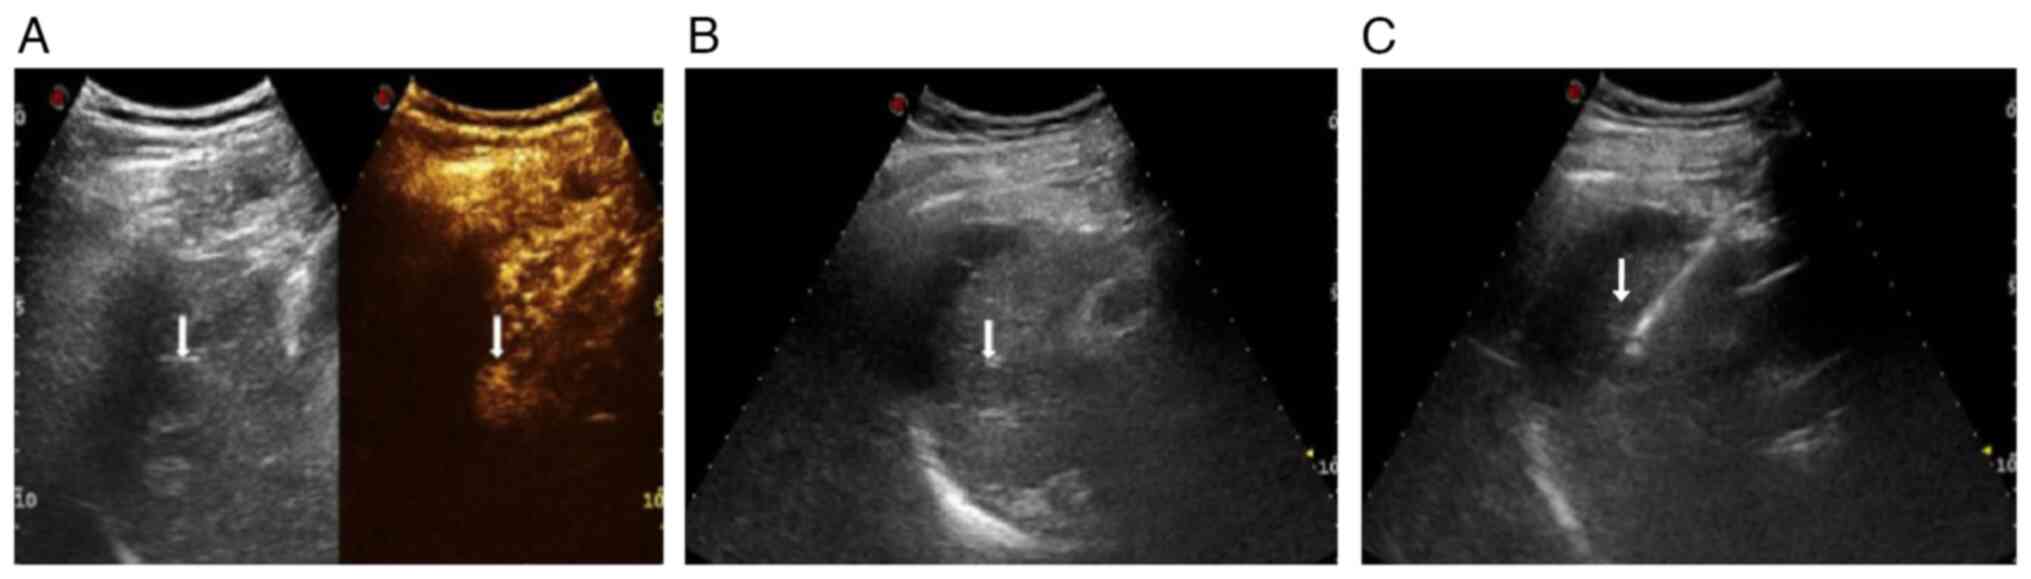

Artificial ascites‑assisted microwave ablation for liver cancer adjacent to the diaphragm and perioperative nursing care

Liver cancer near the deep diaphragm can be difficult to visualize due to the effects of lung gas, which presents a challenge for microwave ablation (MWA). The present study aimed to investigate the feasibility and efficacy of artificial ascites‑assisted MWA for treating liver cancer near the deep diaphragm, as well as the significance of perioperative nursing. A retrospective analysis was conducted on patients who underwent artificial ascites‑assisted MWA for liver cancer located near the deep diaphragm between January 2016 and December 2022. Normal saline was utilized as artificial ascites to safeguard the deep diaphragm during MWA. The study recorded the procedural success rate, incidence of major complications, technical efficacy of ablation and local tumor progression (LTP). A total of 62 lesions in 54 patients were included, with 44 men and 10 women, and a mean (± SD) age of 55.64±10.33 years. The ultrasound image quality scores for liver cancer before and after ascites were 3.57±0.79 and 4.89±0.33, respectively, showing a statistically significant difference between the two groups (t=16.324; P<0.05). No diaphragm injury, skin burns at the puncture site or abdominal hemorrhage occurred during the procedure. A single patient developed right‑sided pleural effusion, which did not require drainage. The complete ablation rate was 94.4% (51/54) at 1 month post‑ablation, with 3 patients experiencing recurrence and receiving additional MWA treatment. The median follow‑up time for the patients in this study was 21 months (range, 12‑45 months), with a LTP rate of 5.6% (3/54). In conclusion, MWA assisted by artificial ascites is a safe and effective treatment for liver cancer near the deep diaphragm. Furthermore, perioperative treatment and rehabilitation of the patients with high‑quality nursing is beneficial.

Figure 1